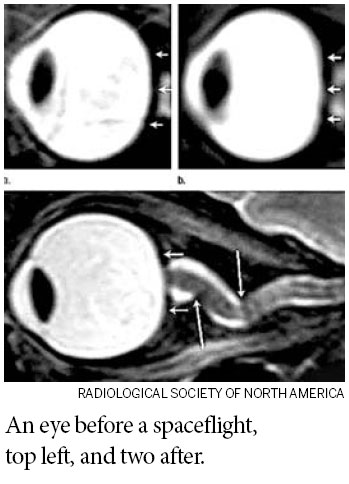

Squashed eyeballs are danger in space